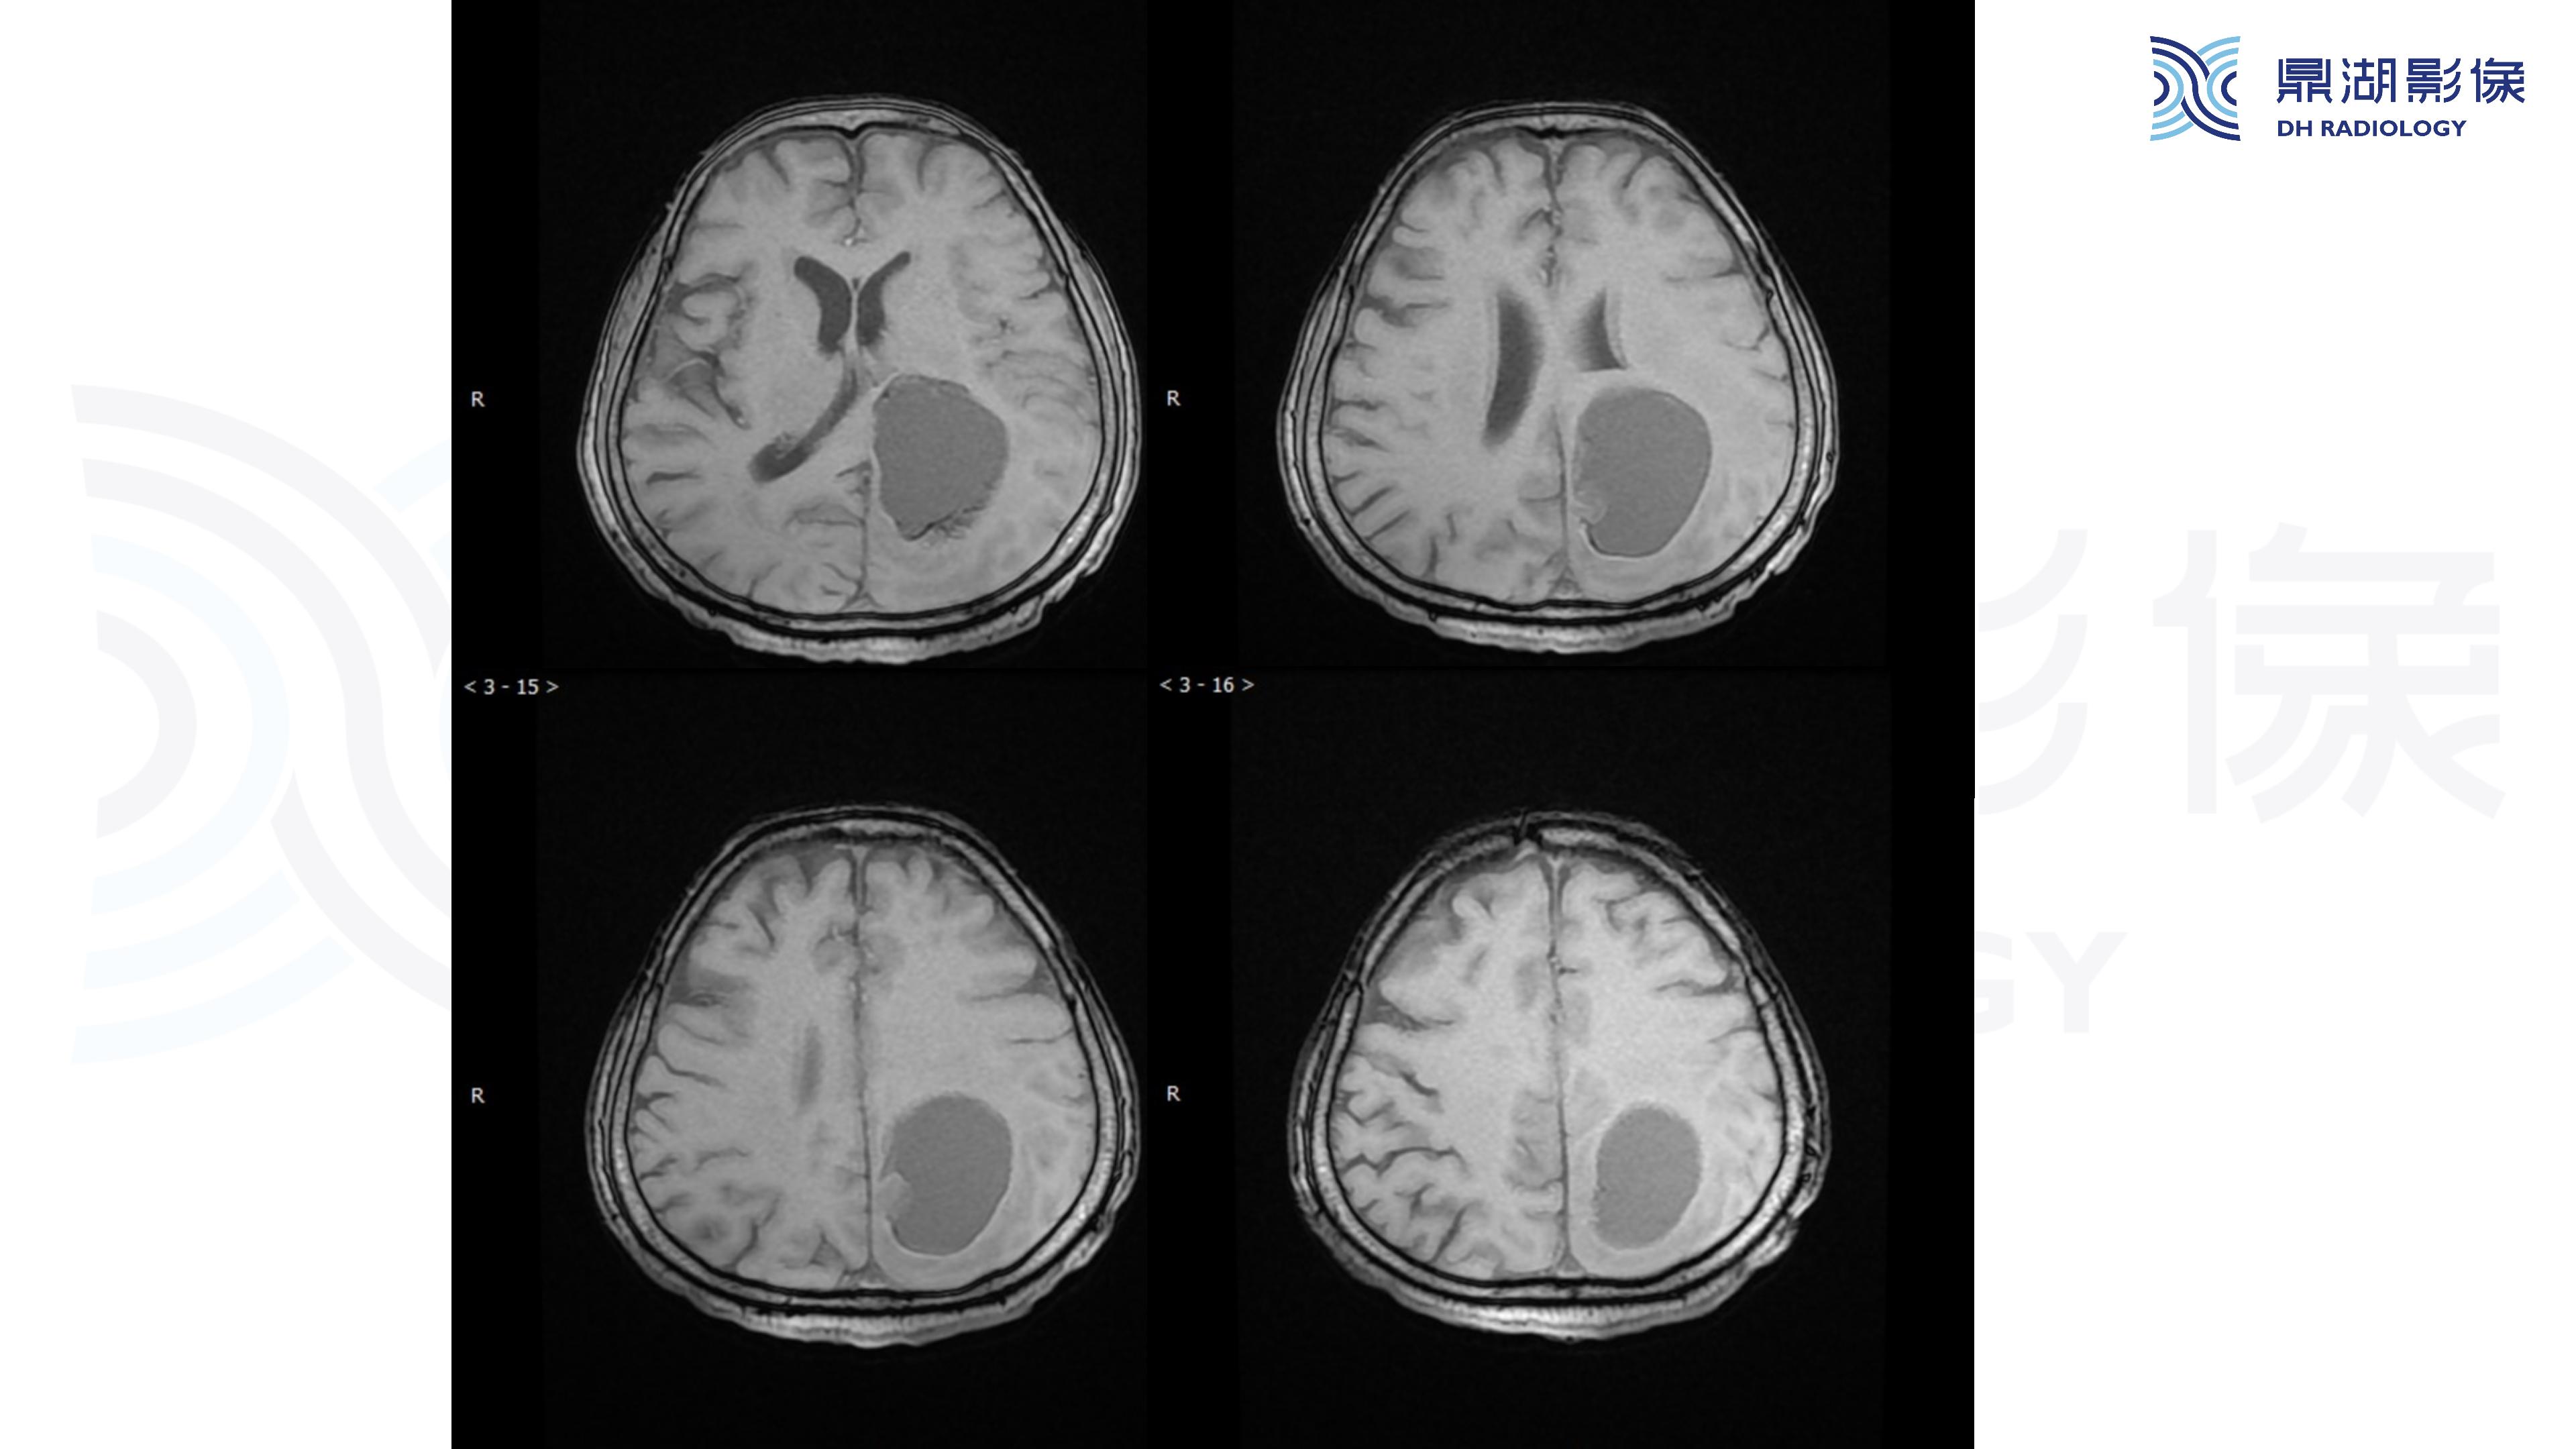

幕上毛细胞型星形细胞瘤(WHO Ⅰ级)